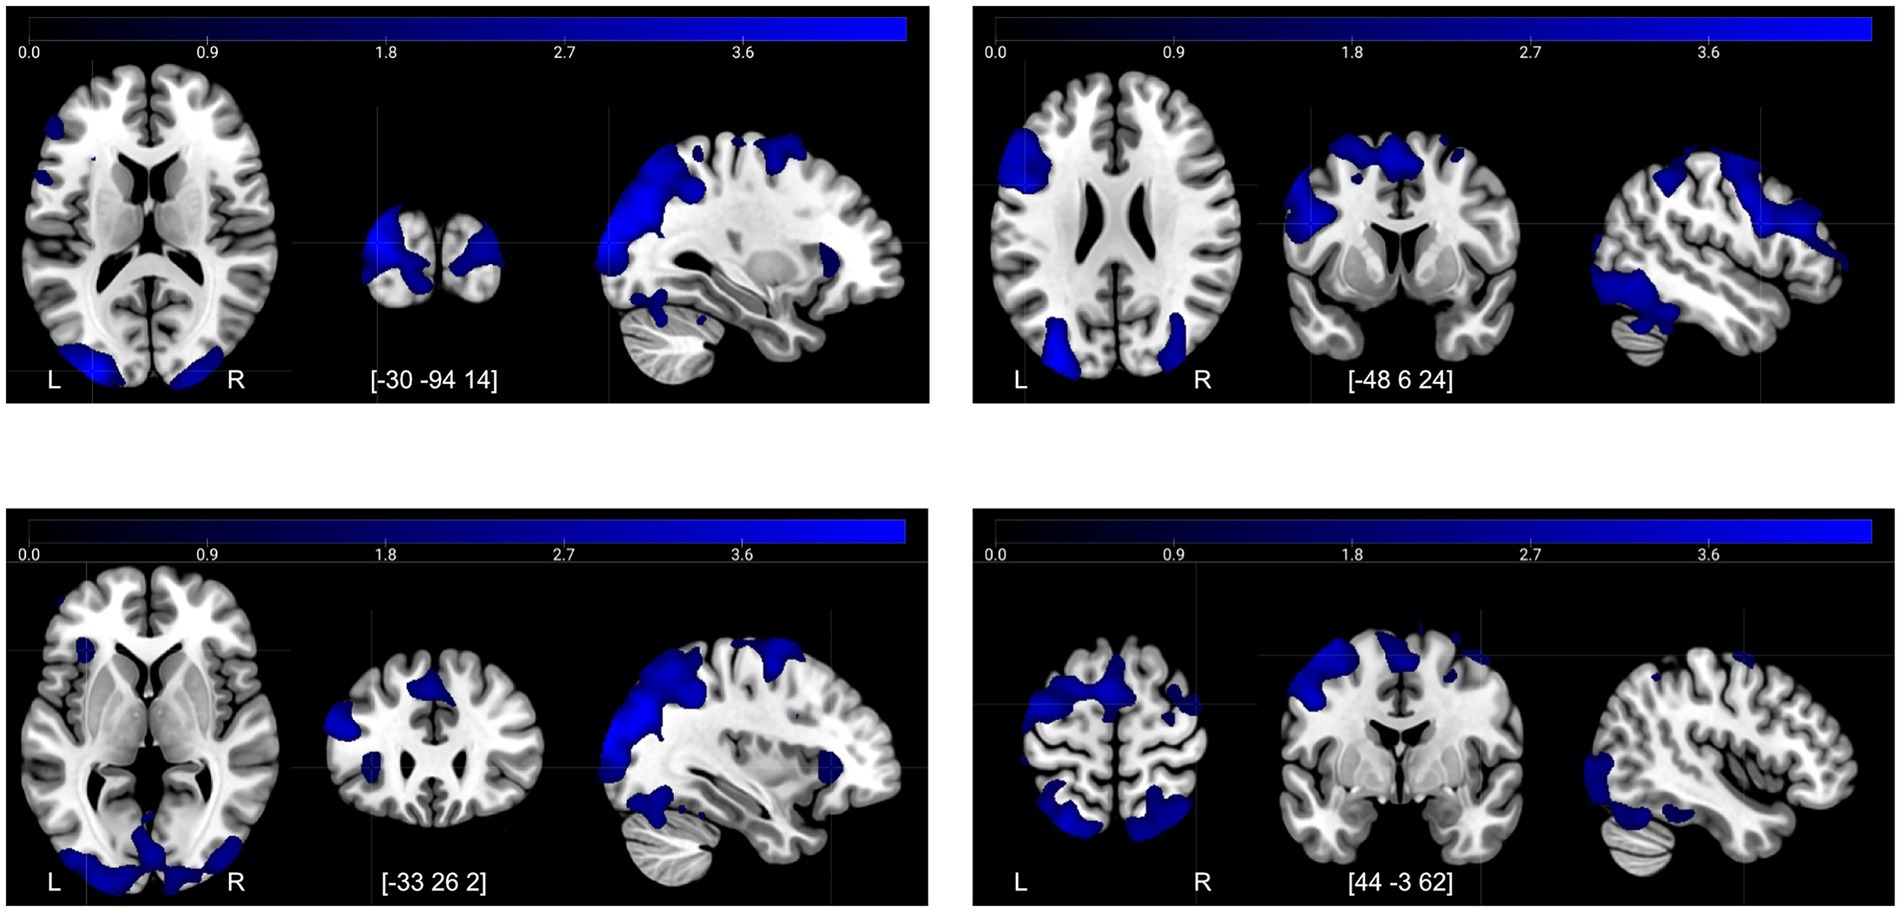

| Decreases T1→T2, retrieval−control | |||||

| Middle occipital lobe | –30 | −94 | 14 | 37,428 | 4,007 |

| Precentral gyrus | −48 | 6 | 24 | 13,557 | 3,237 |

| Anterior insula | −33 | 26 | 2 | 450 | 1,457 |

| Precentral gyrus | 44 | −3 | 62 | 983 | 1,304 |

Significant increases and decreases in brain activity after the control period and intervention period (TFCE FWE-corrected p < 0.05).

Peak = voxel coordinates (MNI-space) of peak activity in the cluster, kE = cluster size, TFCE = critical threshold value to yield a FWE rate of 5%.

The decreases in activity after the control period for Retrieval–Control (Figure 4) corresponded mainly to a frontal-posterior cognitive control network (middle frontal gyrus, superior parietal lobe), visual association areas (cuneus/precuneus), motor areas (dorsal premotor region, presupplementary motor areas), and regions involved in memory retrieval—particularly during recognition tasks (anterior insula/posterior inferior frontal gyrus) (Buckner et al., 1996; Caviezel et al., 2020). In conjunction, these decreases suggest more efficient task-related information processing overall during the second session.